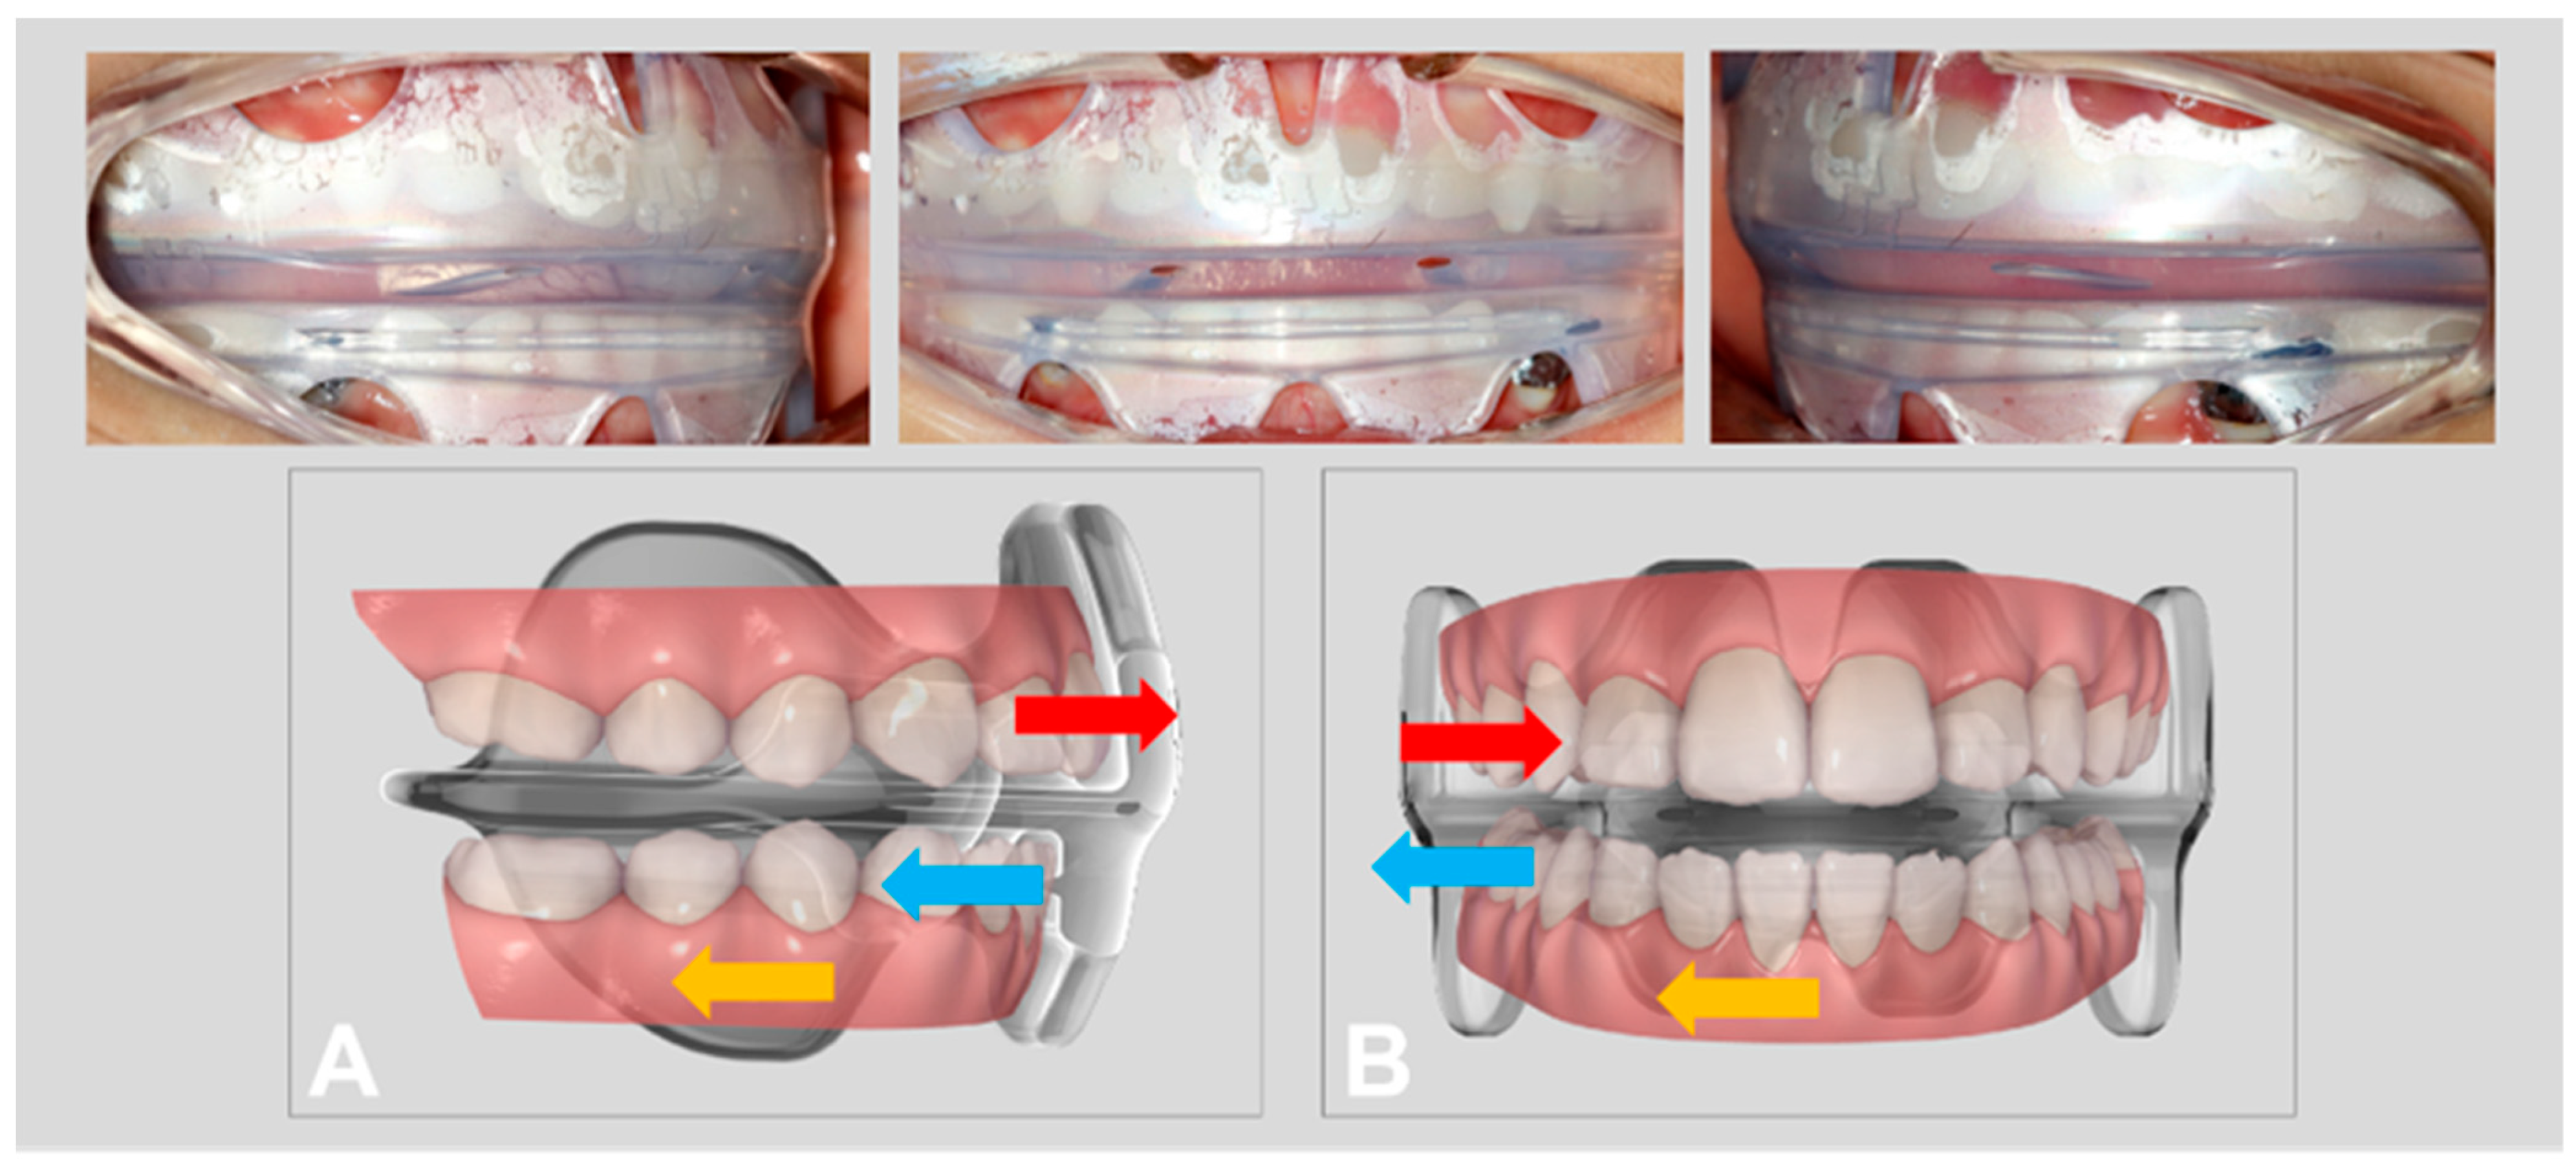

The treatment plan was to induce the mandible to move backward and relieve the occlusion discrepancy of the dental arch with a functional appliance (NOA™-F3) first, combined with myofunctional exercises to break the tongue thrusting habits, and reduce the asymmetric muscular activities with a prefabricated oral screen (NOA™-T) at the same time. The treatment mechanisms of NOA™-F3 for an anterior crossbite and scissor bite are presented in Figure 1. The vertical view and extraoral view of NOA™-T are presented in Figure 2. Once the maxillary and mandibular primary incisors displayed an edge-to-edge bite relationship, a functional dental rehabilitation with a composite inclined plane on an upper anterior segment and the indirect filled technique with the composite resin on posterior teeth were performed to establish a normal occlusion. The patient and her parents provided consent for the publication of data and images related to her treatment for scientific purposes.

Figure 1.

The treatment mechanisms of NOA™-F3 for anterior crossbite. (A): Procline upper incisors (red arrow), retrocline lower incisors (blue arrow), and guide mandible backward (brown arrow) and scissor bite. (B): Lingually moving maxillary posterior teeth (red arrow), buccally uprighting mandibular posterior teeth (blue arrow), and guide mandible to the left side (brown arrow).

The treatment mechanisms of NOA-F3 for an anterior crossbite were to retrocline the lower anterior teeth, procline the upper incisors, guide the mandible backwards (Figure 1), and for the scissor bite to open the posterior deep bite with the occlusal plate, lingually moving maxillary posterior teeth with an elastic vestibular shield, buccally uprighting mandibular posterior teeth with the tongue, and guide the mandible to the left side and establish a proper posterior occlusion. In addition, a myofunctional exercise to break the tongue thrusting habits and reduce asymmetric muscular activities with NOA™-T, which was modified from an oral screen appliance. According to the basic of orofacial myofunctional therapy, it includes the treatment of facial muscle imbalances, training of the tongue posture, and establishing an equilibrium between the tongue, lip, and cheek muscles [18,19,20].